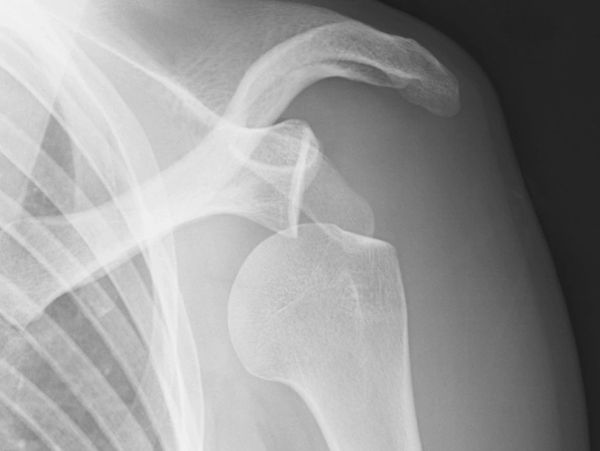

We'll cover glenohumeral subluxations & dislocations, acromioclavicular injuries and instabilities, sternoclavicular instability and the all important (and globally confused) scapular dyskinesis (in all its variations).

Day 1 will bring you up to speed on management of GHJ subluxations & dislocations, initial dislocation management and how it differs for recurrent dislocations. Non-operative vs operative considerations, picking the right surgical procedure (and surgeon), exercise management and necessary progressions.

A patient sees you for advice and rehabilitation options for a recurrent GHJ dislocation (*3), occurring on moderate overhead force. Current rehabilitation has consisted of rotator cuff exercise for the past month in various positions and range of motion drills. She does not feel confident with overhead movement, despite full range of motion and improvements in her exercises. She is unsure about whether her rehab is complete or if she should opt for surgery. The winter season is five months away, and she would prefer to avoid surgery if possible.

She is waiting on an MRA, and has an orthopedic consultation in 6 weeks time.

Examination of the shoulder demonstrates scapular flip with ER and abduction loading. Low shoulder girdle positioning in overhead positions, mild antalgic neck movements and comfort in 90/90 actively.